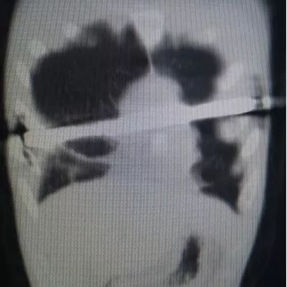

The patient’s anterior chest wall exhibits a prominent depression deformity,characterized by a horizontal groove that affects both sides of the anterior chest wall. There is a surgical scar along the midline and one on the left side, with two scars visible on the right side of the chest wall. A 4x4 cm mass is located on the left chest wall, characterized by darkened skin and noticeable fluctuation upon palpation. The mass extends deep into the intercostal space. Mild scoliosis is also observed. The patient was ultimately diagnosed with grooved chest.

1. Inappropriate Surgical Procedure: grooved chest presents as a relatively flat, horizontal groove-like depression, which differs significantly from the bowl- or cup-shaped depression observed in pectus excavatum. Due to the insufficient height difference between the bottom and edges of the depression, grooved chest cannot provide adequate support points for the Nuss procedure, which is a necessary condition for flipping the bars to elevate the depression during the Nuss procedure, and is directly related to the success of the operation. Therefore, the inappropriate surgical approach is the main reason for the failure of the patient's initial surgery.